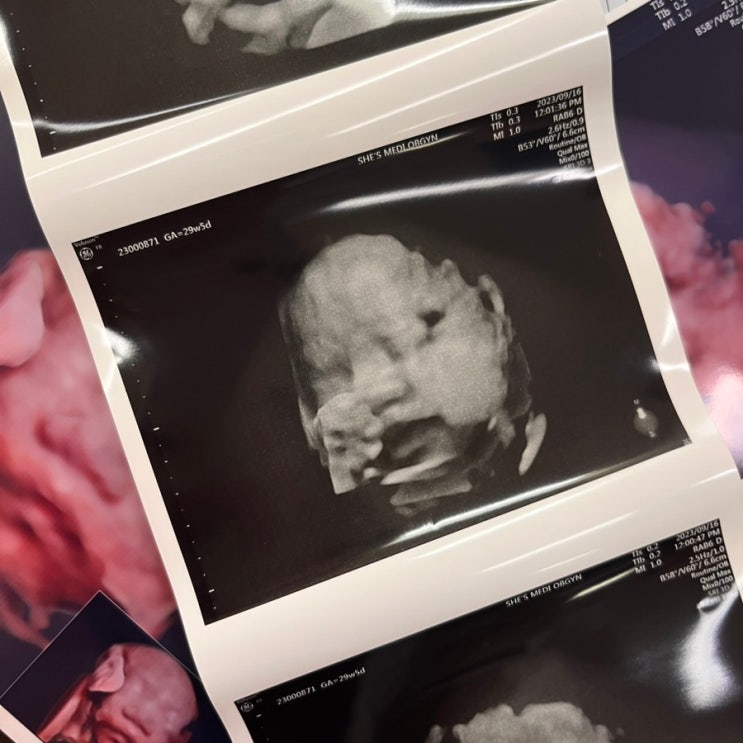

임신 29주 입체초음파 두번째 시도에 성공! 수원 백일해주사

임신 29주 정기검진 임신 25주 임당 검사 이후 한달만에 산부인과 정기검진 가는 날! 근데 나는 임당 확진 ...